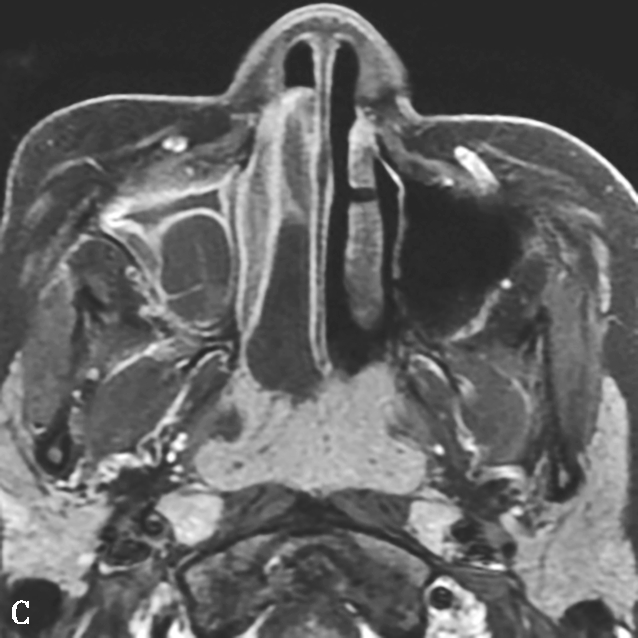

图1-3-20 慢性鼻窦炎

A~C.横断面、冠状面及矢状面CT平扫,示右侧额窦、上颌窦黏膜增厚,窦腔内可见软组织密度影,窦口鼻道复合体狭窄,右侧上颌窦窦壁骨质增生硬化、肥厚;D~F.同一患者横断面MR T 2 WI、T 1 WI及横断面增强T 1 WI,示右侧上颌窦黏膜增厚,呈T 1 WI等信号、T 2 WI高信号影,增强扫描示右侧上颌窦黏膜线样强化